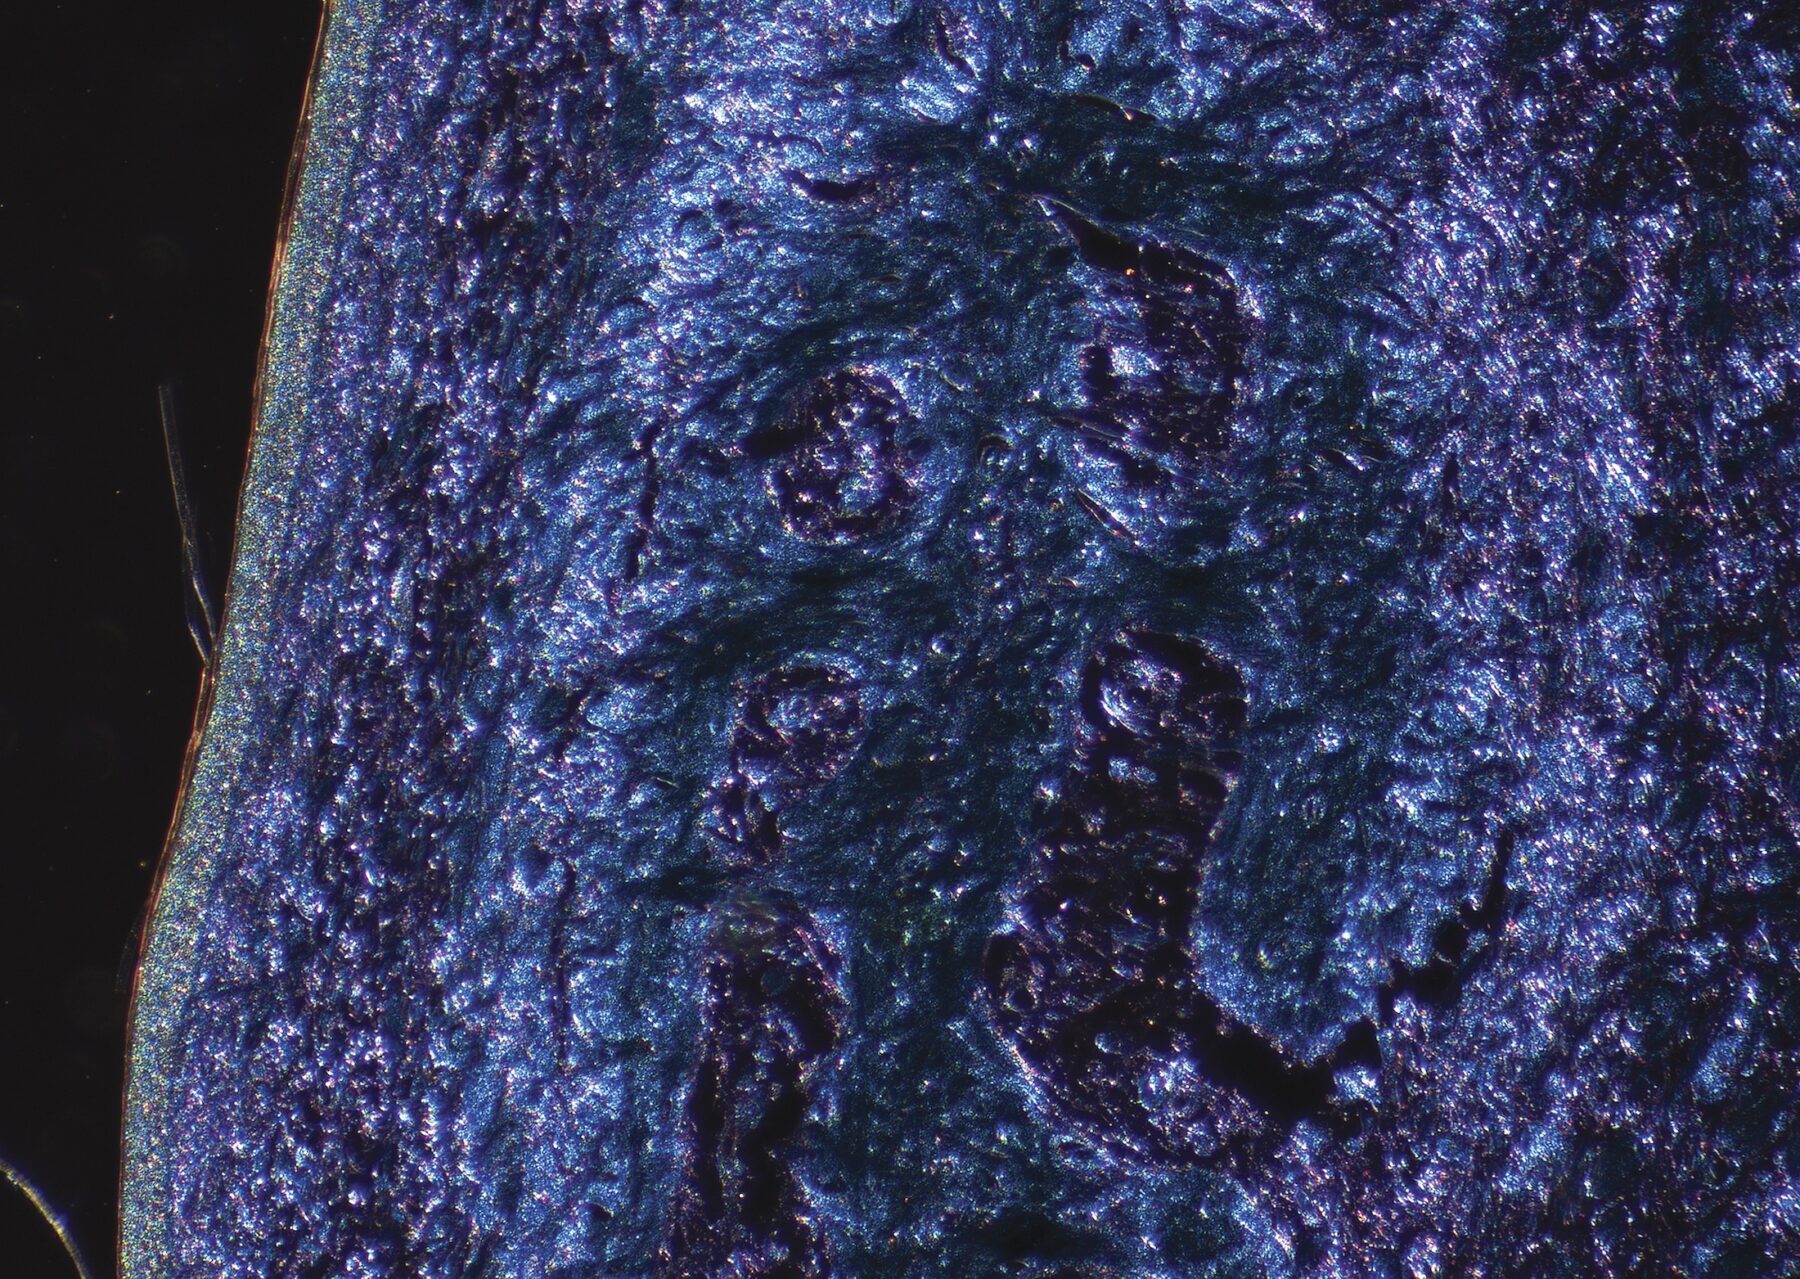

In the first project, Dubansky and his wife, anatomist Brooke Dubansky, knew that the first use of indigo in modern science was for microscopy, to stain cell structures to make them visible under a microscope. Spanish neuroscientist Santiago Ramón y Cajal (1852–1934) was among the early scientists to use a form of plant-based indigo called picroindigocarmine—in which picric acid adds yellow to blend with deep blues and greens in connective tissues—in tissue-staining processes. This method of staining was reported to be beautiful and to have excellent diagnostic value, but it became outdated before the invention of color photography, so no visual record of it exists. The Dubanskys were curious to find out what it looks like.

They began experimenting with a modified form of picroindigocarmine to stain archived slides of histological tissue. After some trial and error, they achieved aesthetically pleasing results. This microscopy history added an often-overlooked dimension to the story of indigo and is an intriguing example of the intersection of biology and textile chemistry, which Forsyth was excited to include in the exhibition. When Ben Dubansky initially joined Intersections 2021, he envisioned his role as a science advisor, maximizing the scientific content in the Art & Science Collide exhibitions. He never imagined his work would be featured in a show.